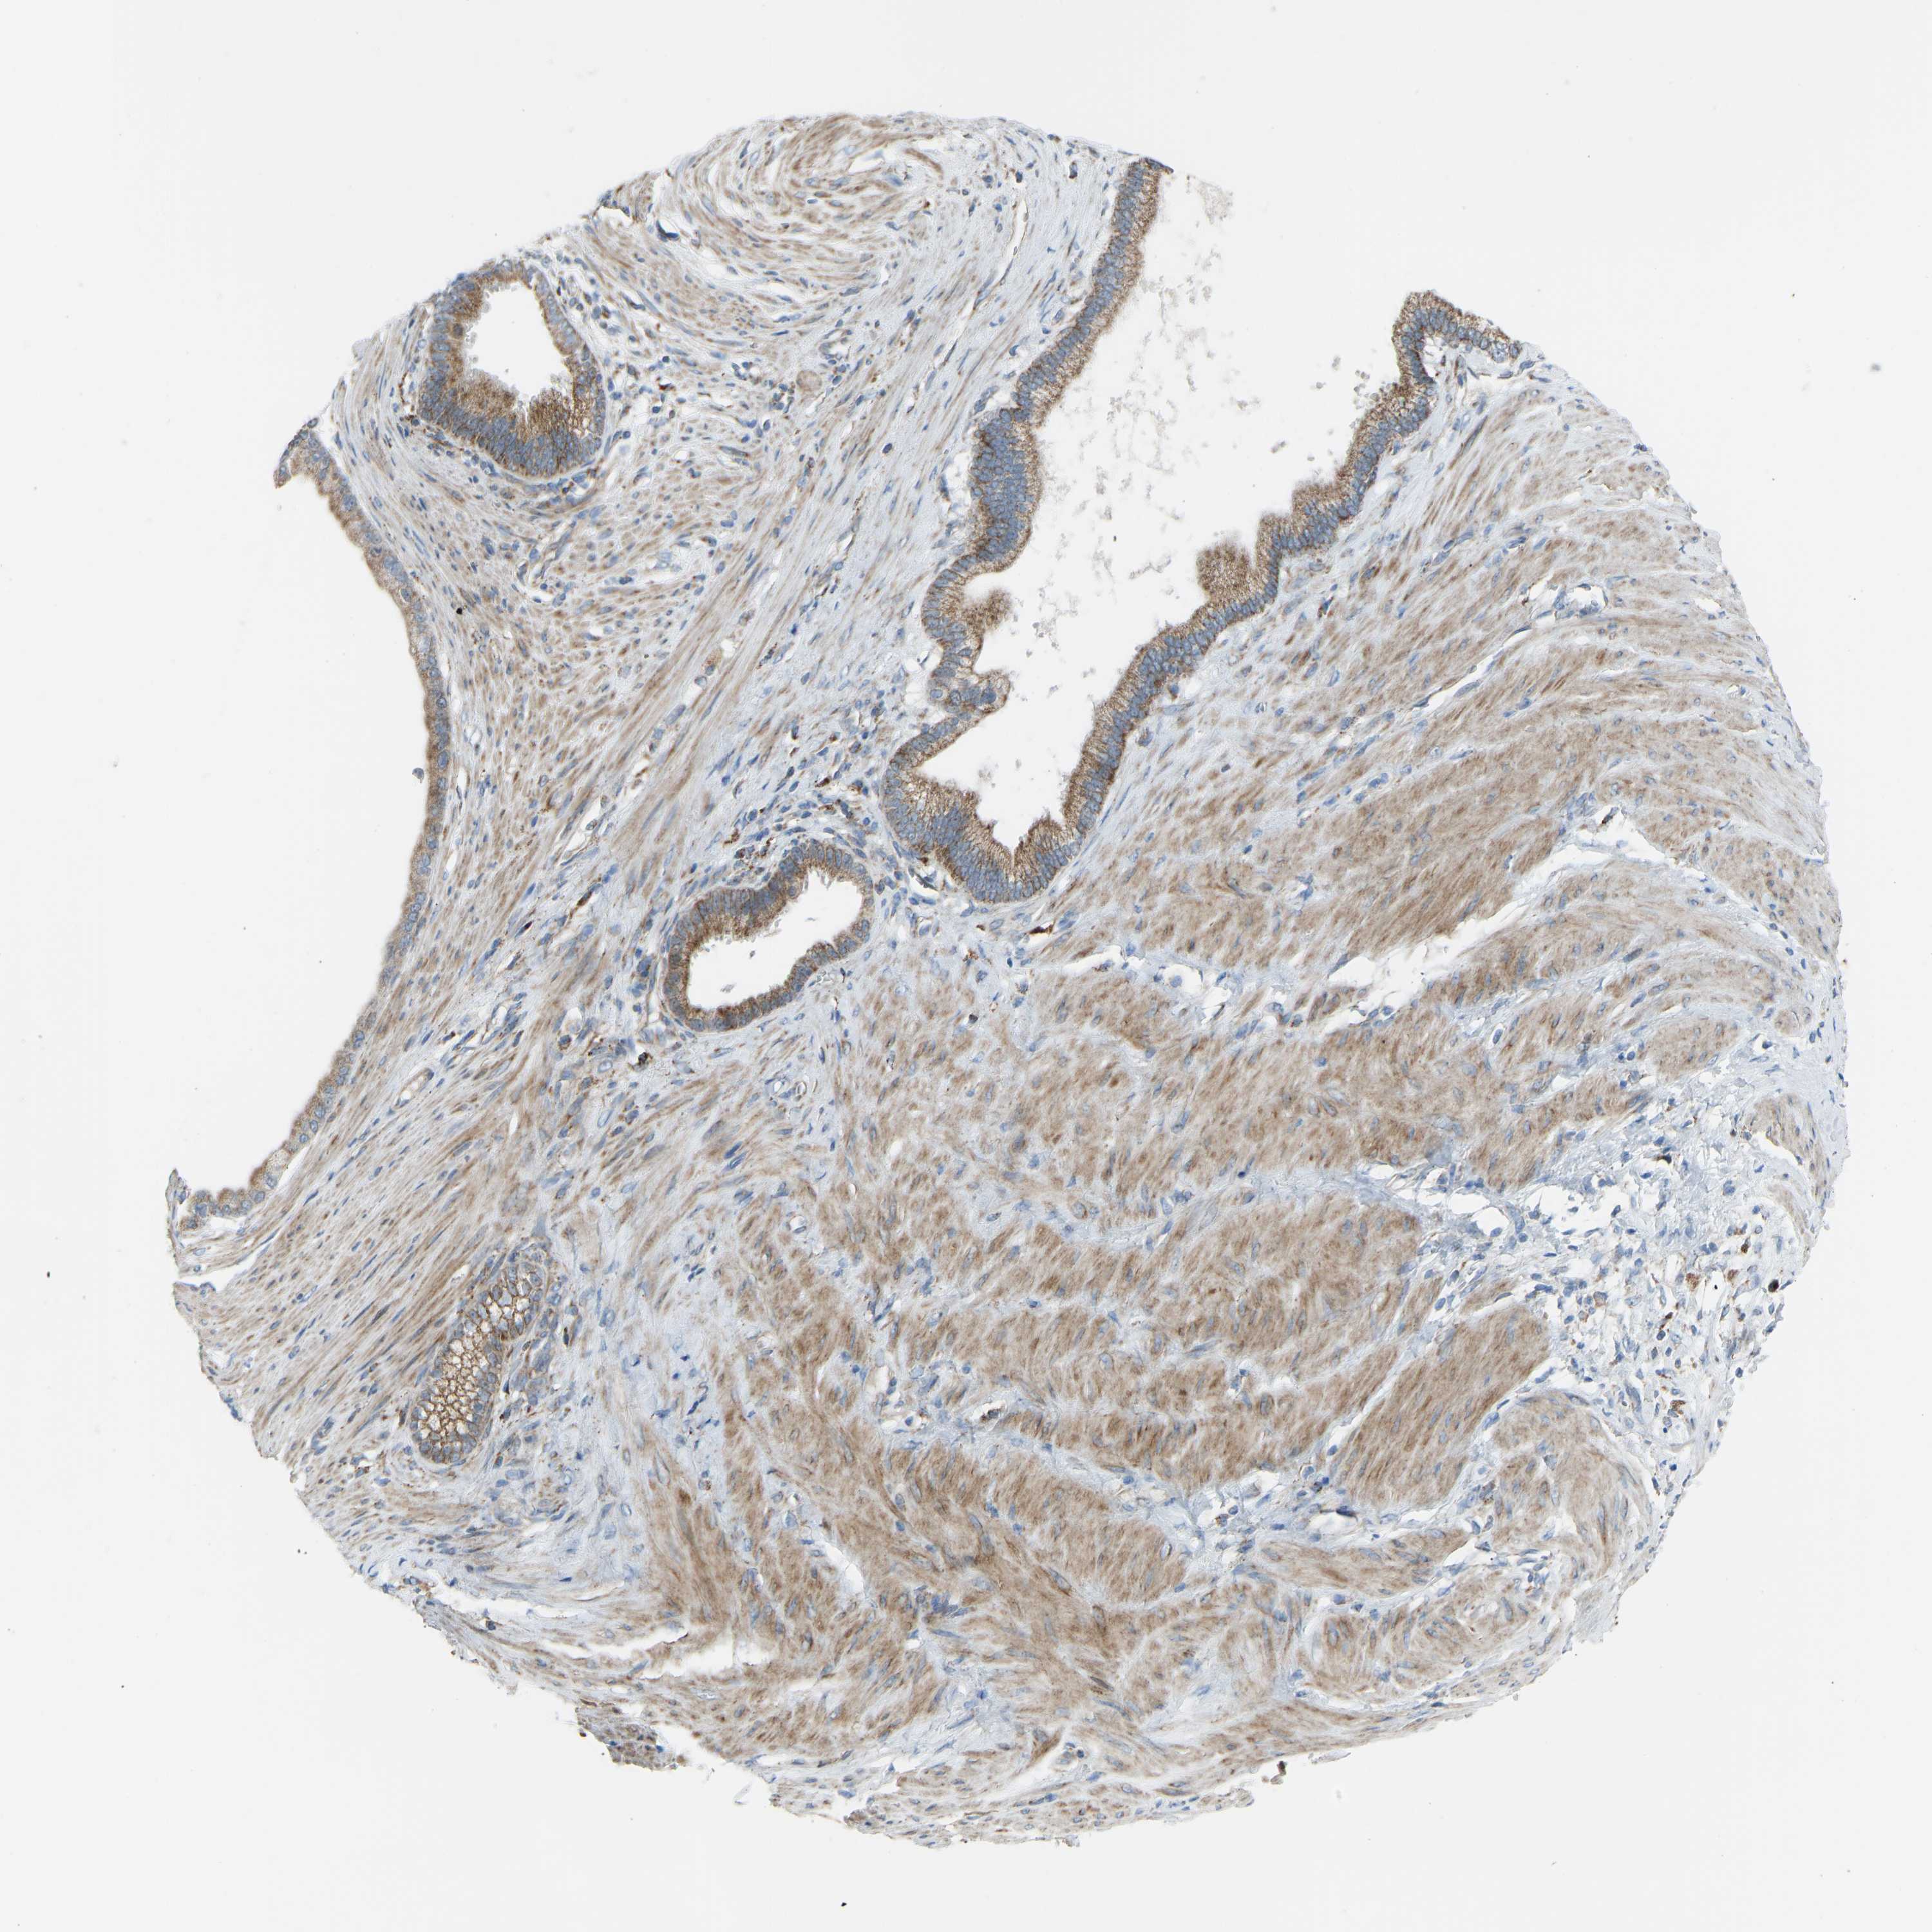

PANCREATIC CANCER - Protein expressioni

A mouse-over function shows sample information and annotation data. Click on an image to view it in a full screen mode. Samples can be filtered based on level of antibody staining by selecting one or several of the following categories: high, medium, low and not detected. The assay and annotation is described here.

Note that samples used for immunohistochemistry by the Human Protein Atlas do not correspond to samples in the TCGA dataset.

Antibody stainingi

Antibody staining in the annotated cell types in the current human tissue is reported as not detected, low, medium, or high, based on conventional immunohistochemistry profiling in selected tissues. This score is based on the combination of the staining intensity and fraction of stained cells.

Each image is clickable and will lead to virtual microscopy that enables deeper exploration of all samples and also displays staining intensity scores, fraction scores and subcellular localization as well as patient and tissue information for each sample.

Antibody HPA016552

Staining

High

Medium

Low

Not detected

Intensity

Strong

Moderate

Weak

Negative

Quantity

>75%

75%-25%

<25%

None

Location

Nuclear

Cytoplasmic/membranous

Cytoplasmic/membranous,nuclear

Adenocarcinoma, NOS